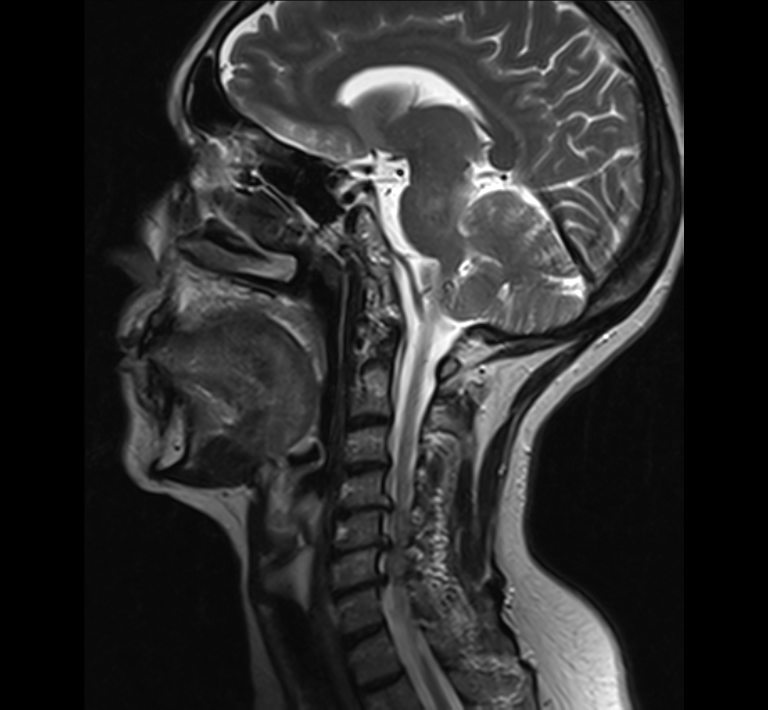

Prueba diagnóstica no invasiva que consiste en la obtención de imágenes de alta definición anatómica del cuello mediante el empleo de un campo electromagnético y ondas de radio (con un emisor y un receptor). No utiliza radiación ionizante. Indicaciones: sospecha de tumor, infecciones, ganglios.